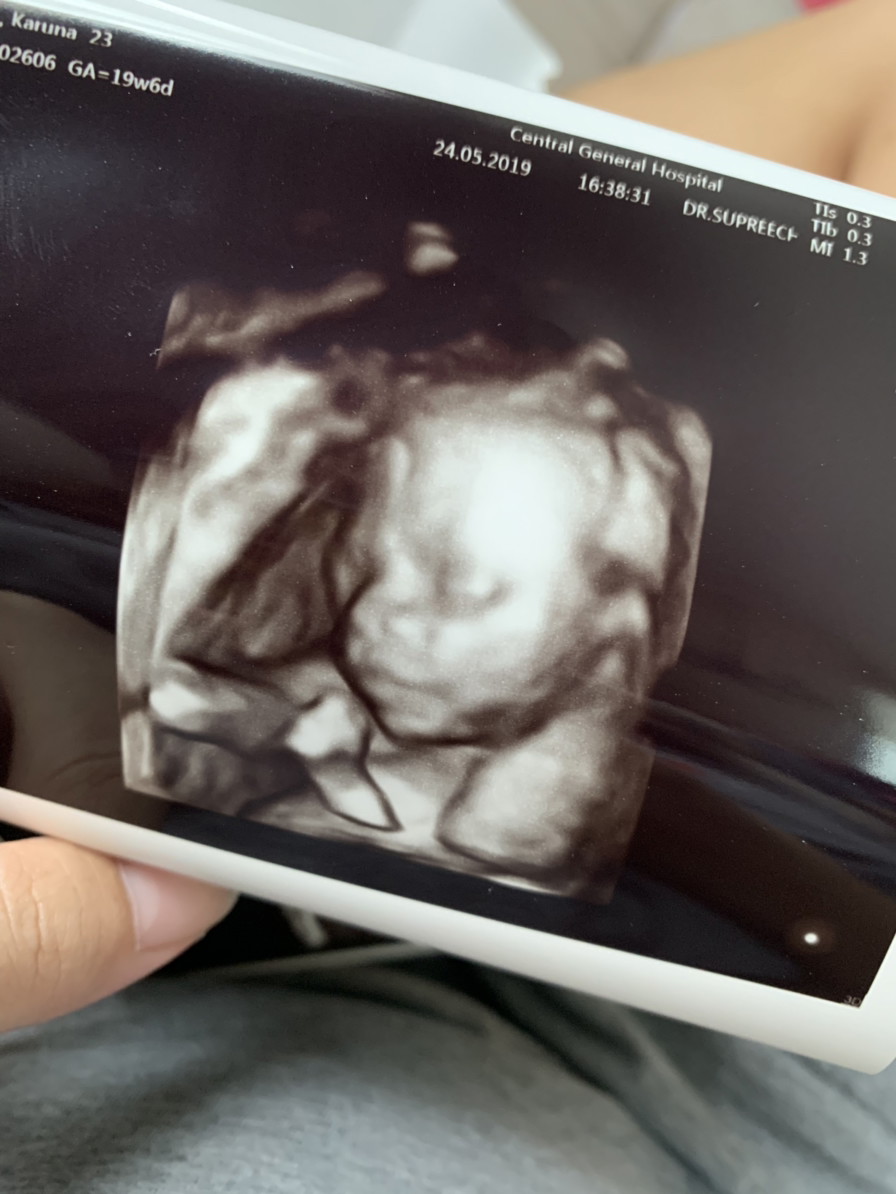

อันนี้ตอน 19w6d คะ